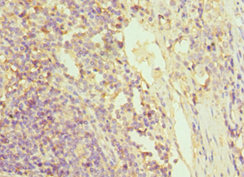

Immunohistochemistry of paraffin-embedded human colon cancer using CSB-PA009939ESR2HU at dilution of 1:100